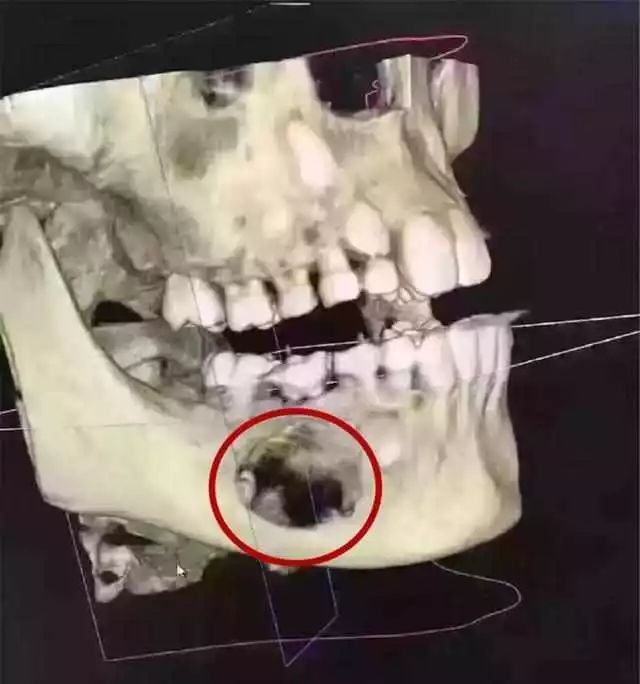

先看这位9岁孩子的牙片

这是一位9岁的小姑娘,因父母没有重视乳牙护理和龋齿治疗,那颗乳牙下面的颌骨大面积吸收!当然,囊肿造成的乳牙根尖周炎,也可能是这种吸收的可能原因之一(由于没有详细资料和医生的诊断)。